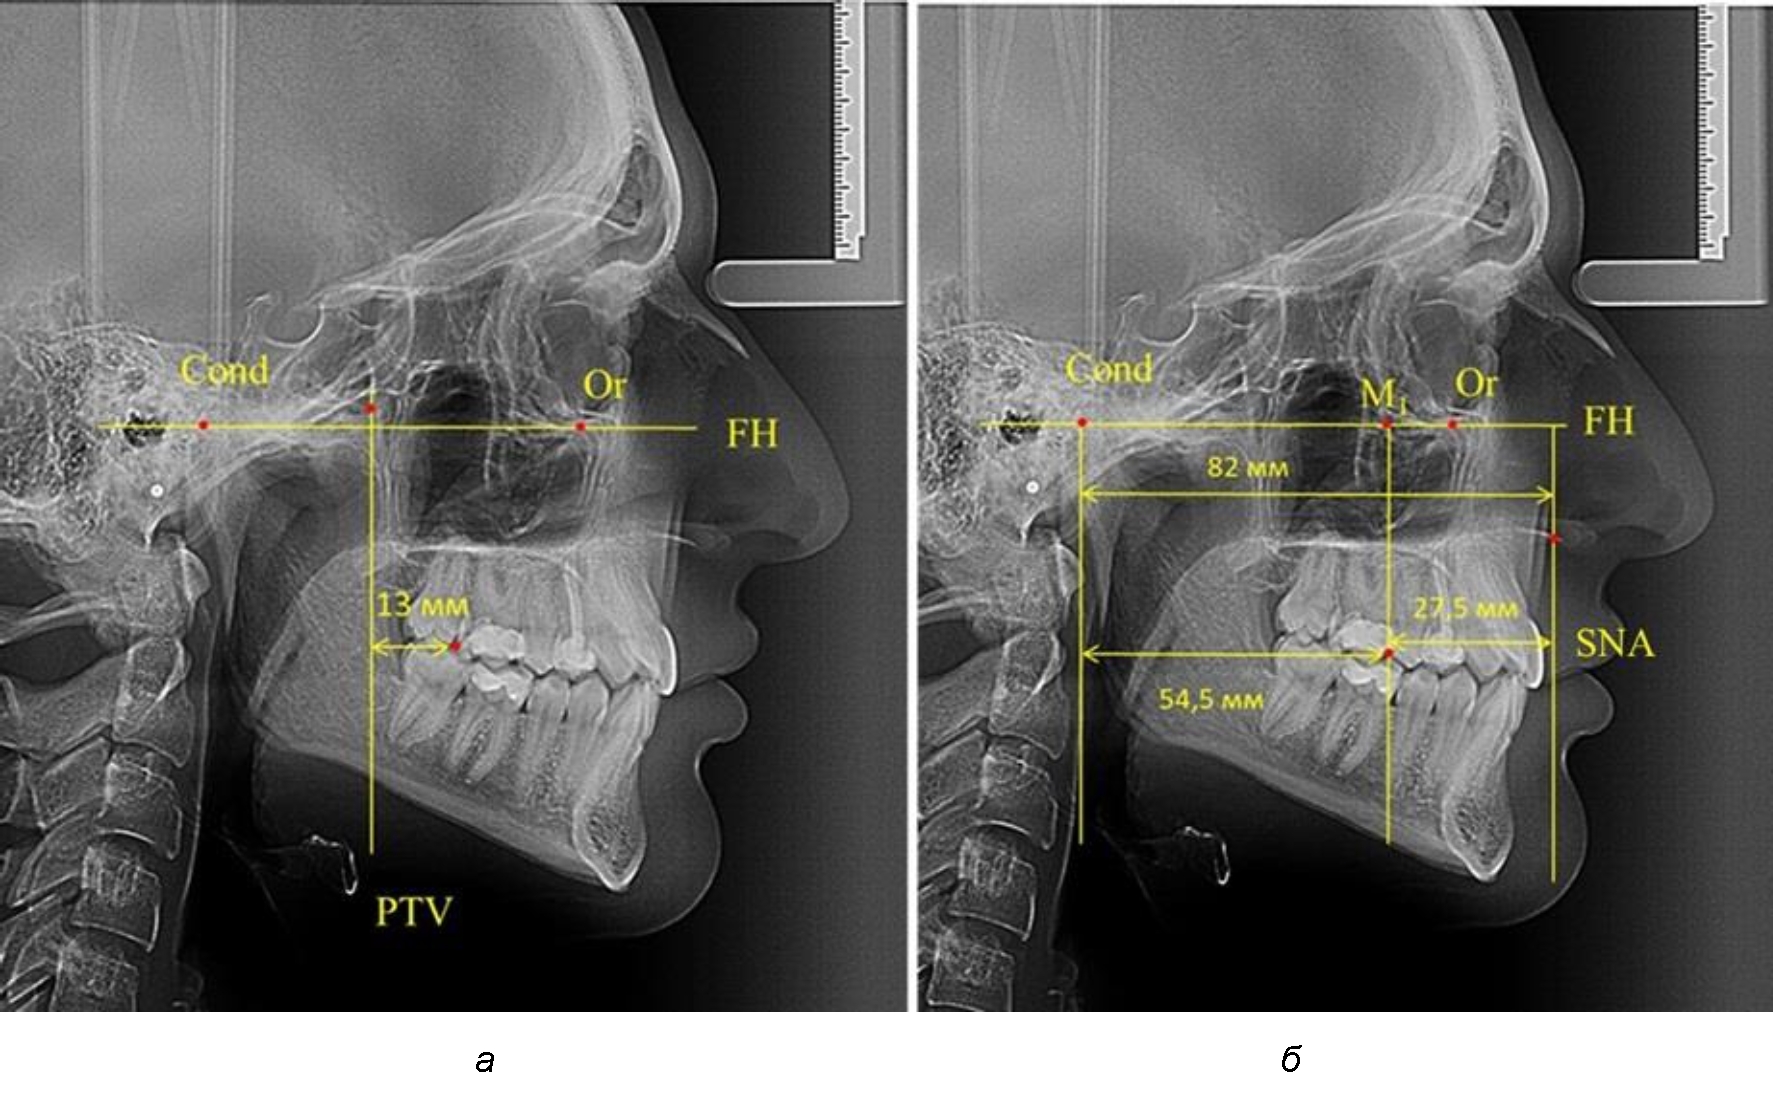

Так, при расстоянии от крыловидной вертикальной плоскости PTV до дистальной поверхности верхнего первого постоянного моляра в 13 мм сагиттальный размер гнатического отдела был 82 мм. При этом отношение кондилярно-спинального расстояния к кондилярно-молярному размеру (54,5) было близким к коэффициенту 1,5, что представлено на рис. 2.

Рис. 2. Особенности положения первых моляров по R. E. McDonald (а) и по предложенному методу (б) при уменьшенном молярно-крыловидном расстоянии